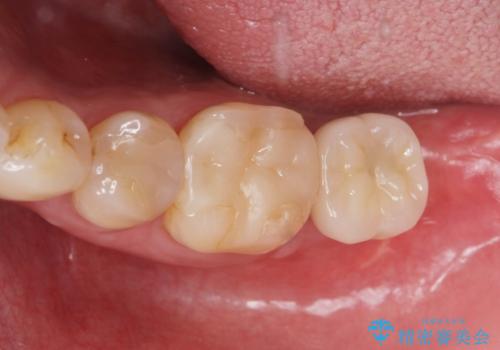

歯からの異臭 虫歯の再発からのインプラント治療

- 「歯から異臭がする。」とのことで相談に来院されました。

X線検査を行ったところ、セラミッククラウン下に虫歯が再発し、歯の破折も認めました。

歯の抜去を行い、骨の造成を含めたインプラントによる咬合機能の回復を図ります。

X線を撮ることで、外から見てもわからない、歯の問題点をより正確に把握することができます。